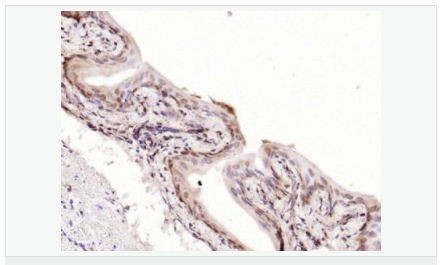

交叉反應:Human,Mouse,Rat(predicted:Dog,Pig,Cow,Horse,Sheep) 推薦應用:WB,IHC-P,IHC-F,IF,Flow-Cyt,ELISA

產品應用WB=1:500-2000 ELISA=1:5000-10000 IHC-P=1:100-500 IHC-F=1:100-500 Flow-Cyt=1μg /test IF=1:100-500 (石蠟切片需做抗原修復)